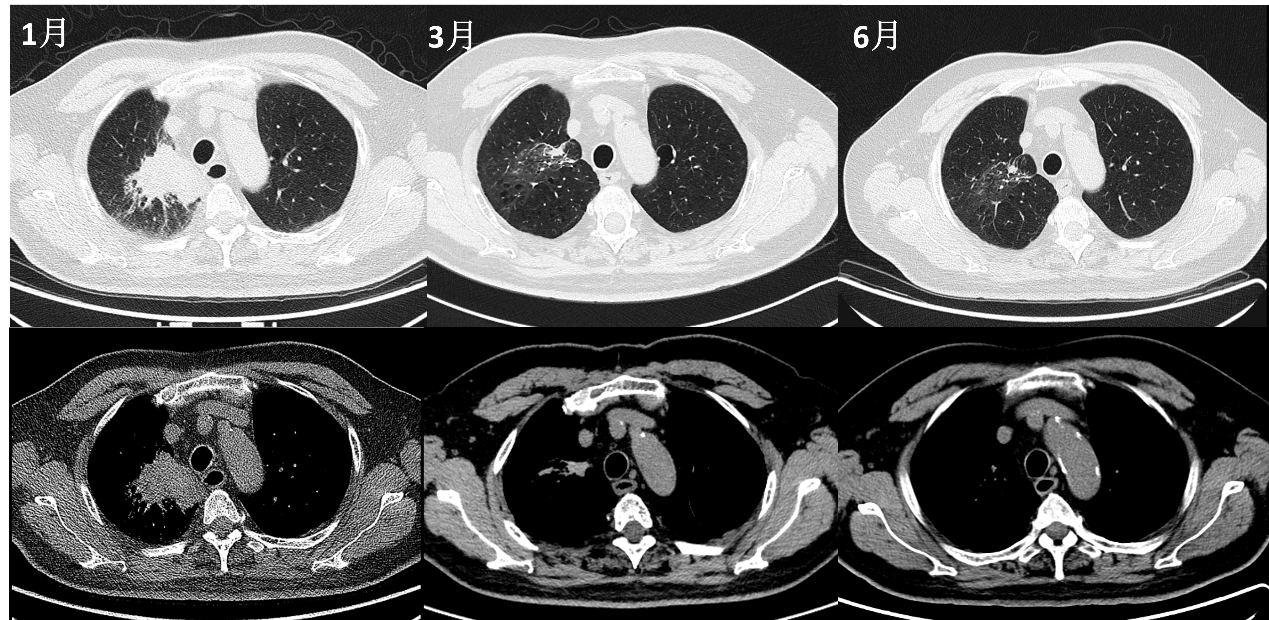

2025-02,待患者呼吸道症状缓解,开始第一程舒格利单抗+白蛋白紫杉醇+卡铂方案,总计治疗6疗程,期间患者耐受性良好。2025-06,复查胸部CT提示病灶明显缩小,喉镜提示未见新生物。

图6. 2025-06疗效评估

影像科:2025-03CT示右肺病灶缩小,疗效评价为PR。6程化疗后复查PET/CT仍存在小结节,在实体瘤的疗效评价中,只能判断为PR。但是PET/CT提示病灶糖代谢未见异常,而且CT无强化,可以考虑为坏死,但此时仍不能确定为CR。